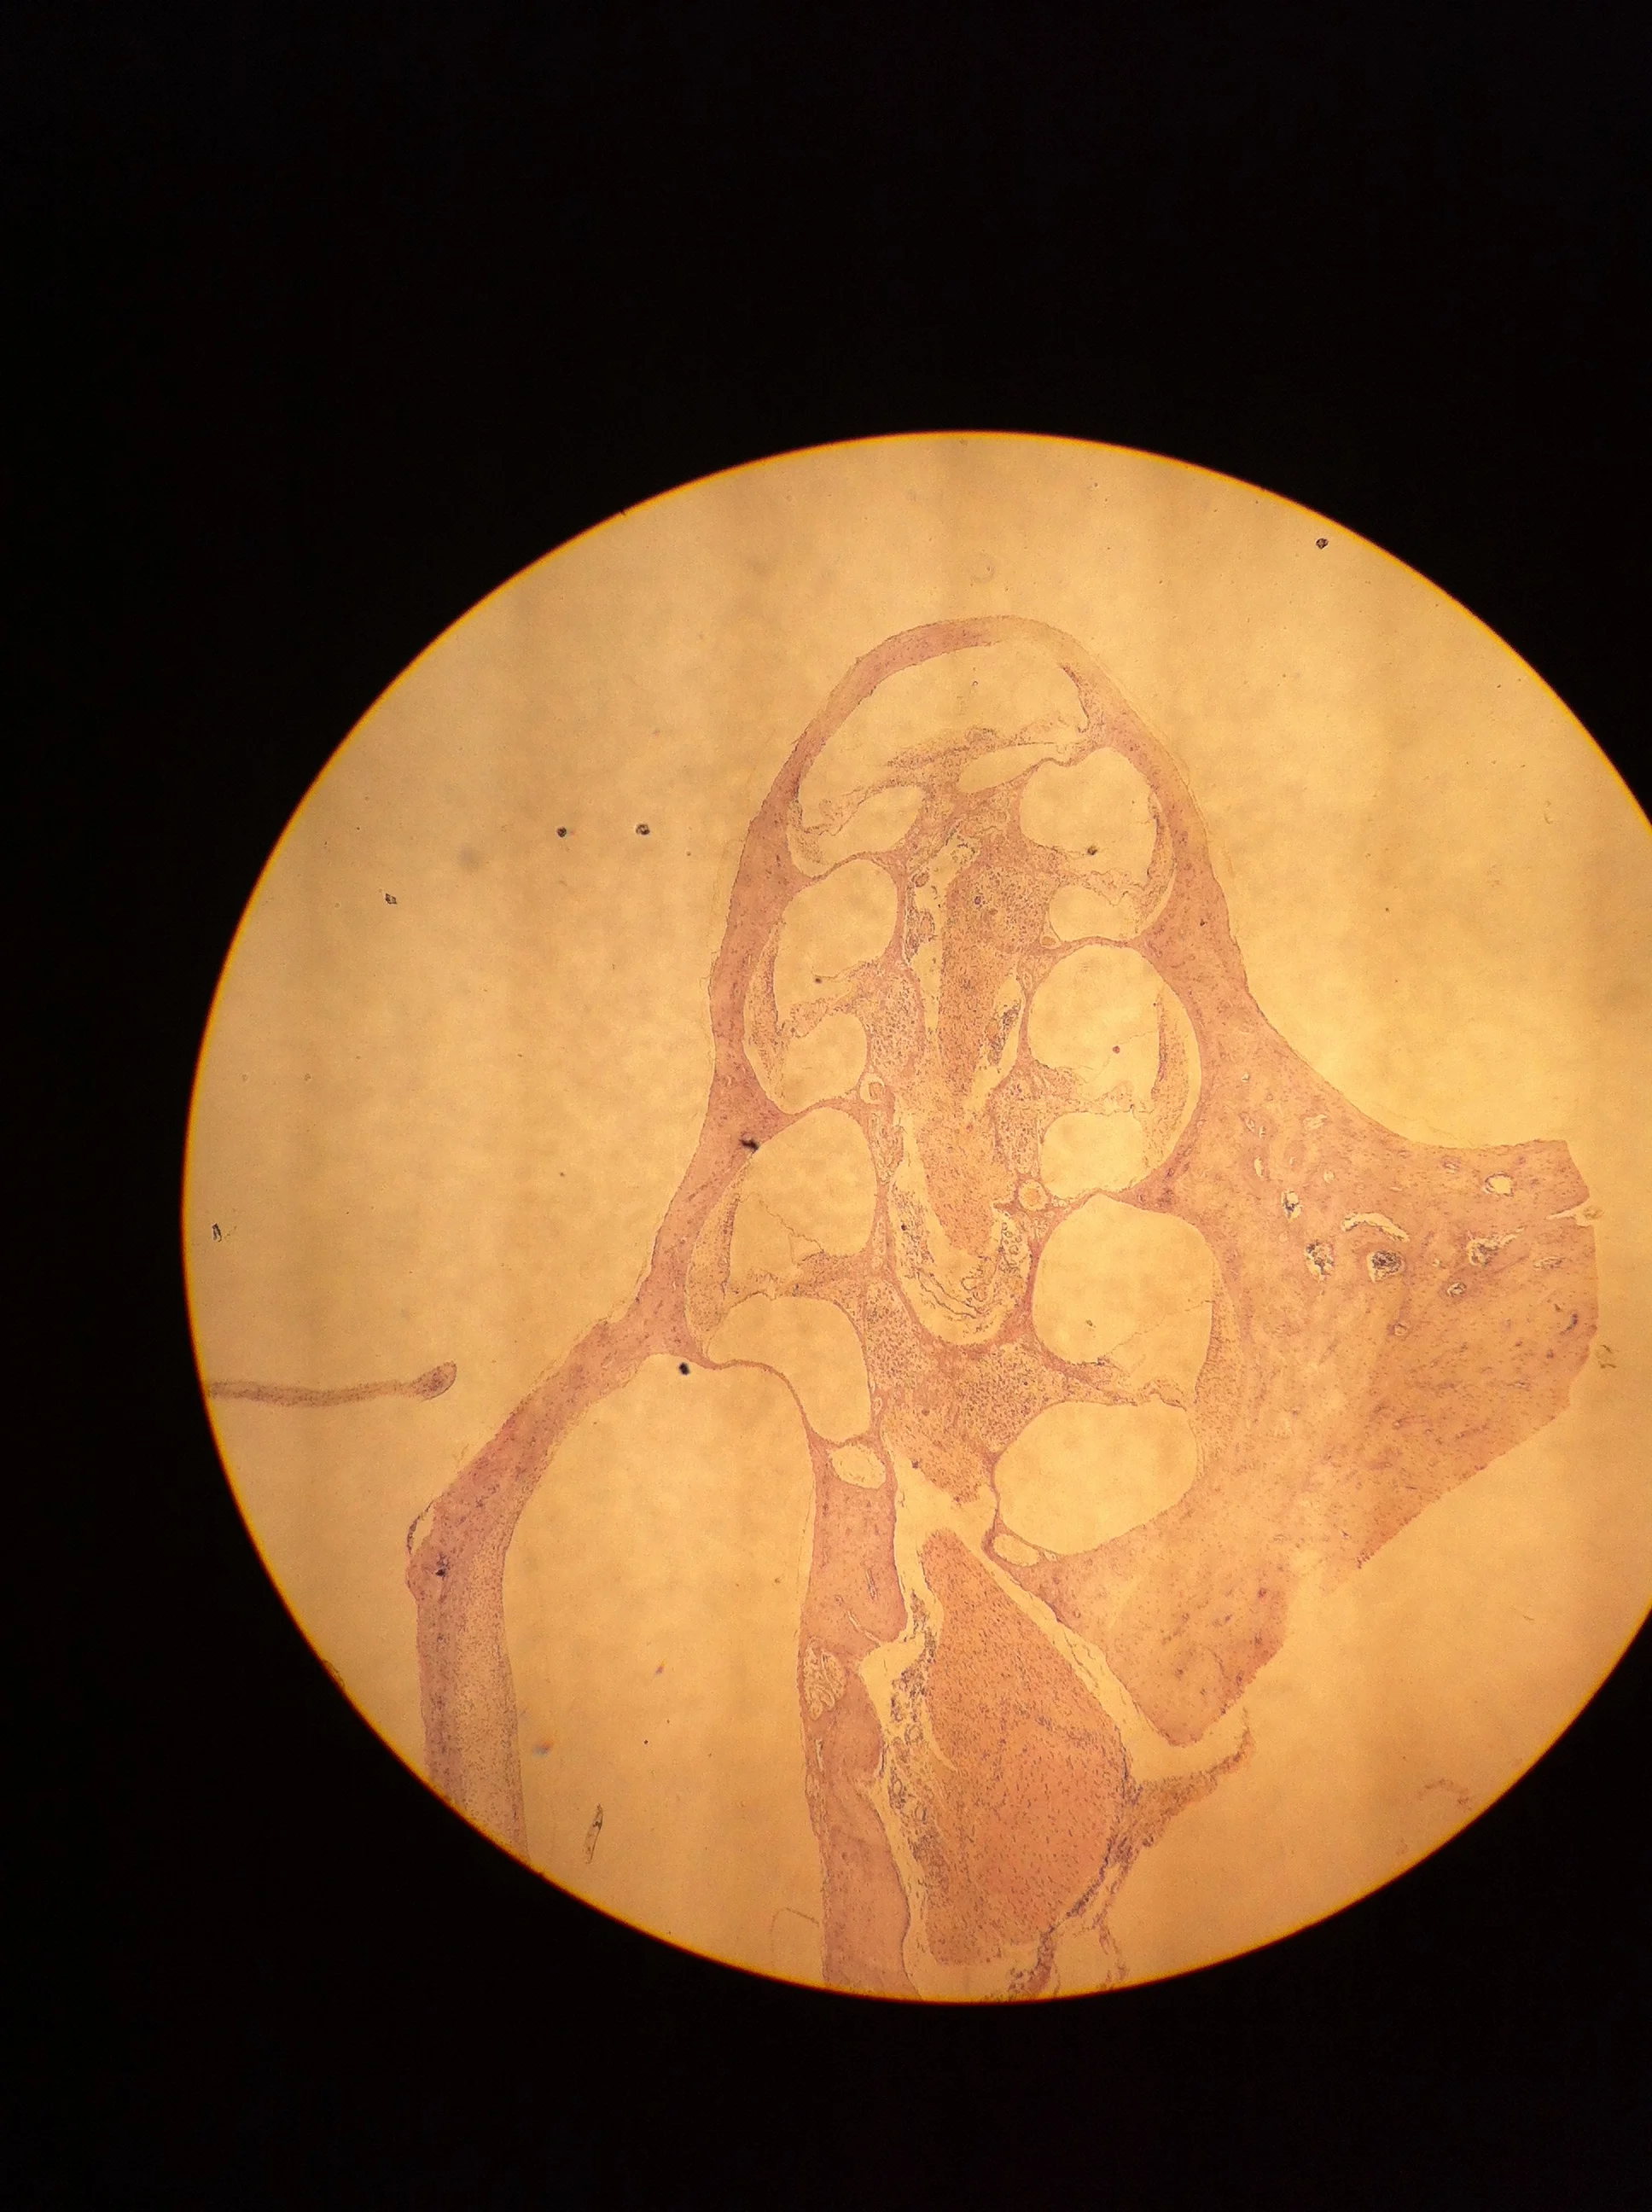

Ear 40X